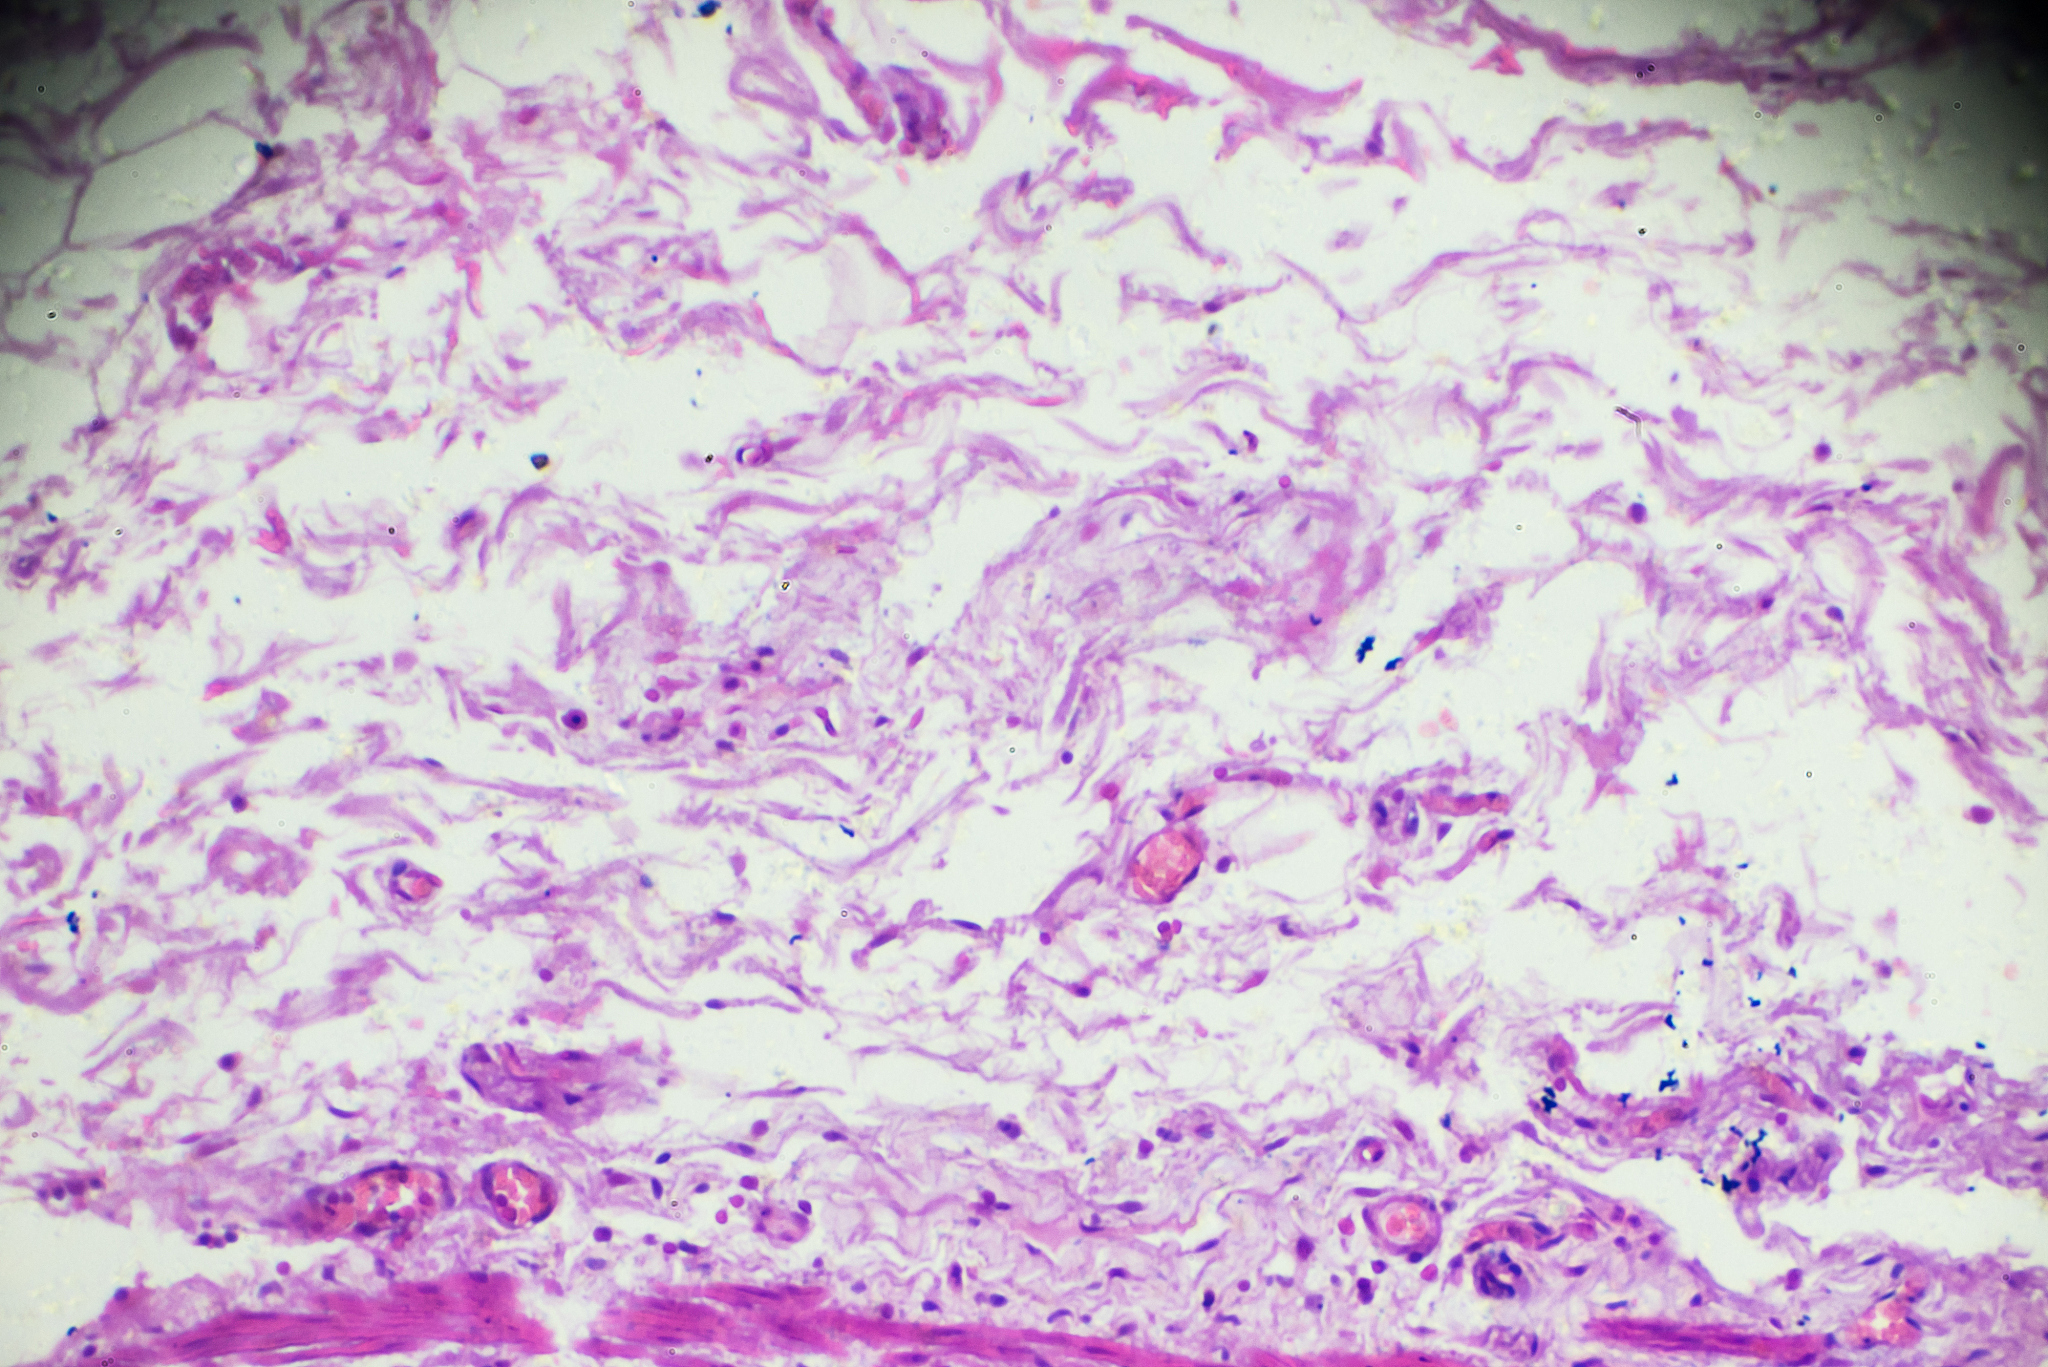

其次,胃镜可以采集组织样本进行病理学检查。胃黏膜内的癌变通常会伴随有细胞学和组织学的变化,胃镜可以采集组织样本进行病理学检查,以确定是否存在癌细胞。这种方法准确性很高,可以帮助医生确定病变的类型和严重程度。